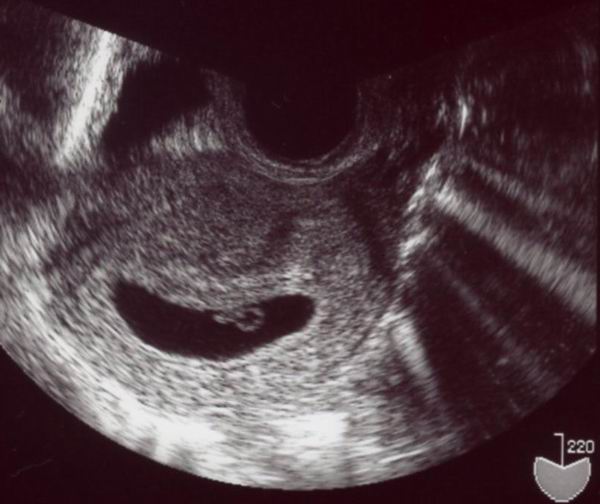

で,お腹の中の様子は…。

この静止画像じゃ何が何だかよく分からないのですが,

モニターで動く様子を見たら感動ですよ!!

前回はお医者さんにしか分からなかった「動いてますよ」の様子。

今回は私にもはっきり分かりました!

もう心臓が出来上がってるんですね。

トクトク言う様子がよく分かりましたよ

まだ「胎児」までは成長してなくて「胎芽(たいが)」って

いうんですがね。いっちょまえに大したものです。